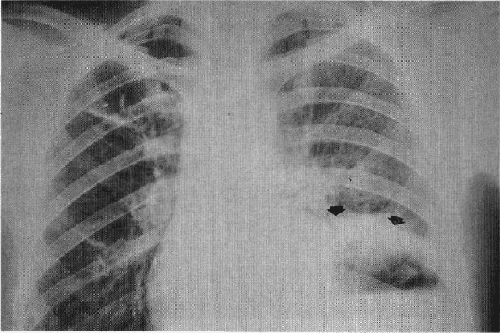

Al examen abdominal se observaba marcada distensión, peristalsis abolida, dolor a la palpación del epigastrio que no permitía la palpación profunda. Se realiza hidratación y colocación de sonda nasogástrica y se practican los siguientes exámenes paraclínicos: Hb: 12.8 g%; Hcto: 38%: Leucocitos 17.800/mm. La radiografía del tórax mostró neumoperitoneo masivo con elevación de los hemidiafragmas, y aire subdiafragmático que desplazaba al hígado hacia abajo y hacía la línea media (Fig. 1). La radiografía simple del abdomen mostró gran dilatación gástrica con traslocación de la curvatura mayor a la derecha, imagen compatible con vólvulo gástrico (Fig. 2). Con estos hallazgos clínicos y paraclínicos se plantea la impresión diagnóstica de abdomen agudo secundario a perforación de víscera hueca, con vólvulo gástrico agudo. Se realiza laparotomía exploratoria por la línea media, encontrándose gran dilatación del estómago que presentaba un vólvulo organoaxial; al destorcerlo se observó una perforación gástrica de aproximadamente 2 cm en la curvatura menor, con laxitud de los ligamentos gastroesplénico y gastrocólico; se realizó reparación de la perforación y gastropexia de la curvatura mayor al diafragma y al peritoneo parietal anterior. La paciente se mantuvo estable durante el acto quirúrgico y la evolución postoperatoria fue satisfactoria; se dio de alta al décimo día postoperatorio.

| Fig. 1. Radiografía del tórax que muestra neumoperitoneo masivo, con elevación de los hemidiafragmas (flechas grandes) y desplazamiento del hígado hacia abajo y hacia la línea media (flecha pequeña). |